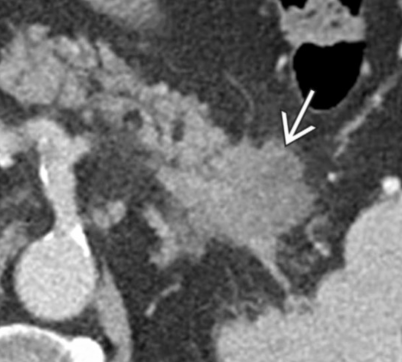

- Masse hypodense mal délimitée (formation de tissus fibreux avec le tissu sain par réaction desmoplastique)

- Visible en Hypodense au temps pancréatique (40s) et veineux (70s)

- Infiltre le rétropéritoine++

- Infiltration veineuse: Contact, engainement, sténose, occlusion